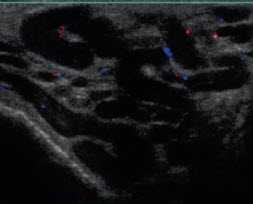

- Варикоцеле

- Клиническая классификация (Dubin-Amelar, 1978)

- 1 степень - определяется при пробе Вальсальвы

- 2 степень - определяется в покое

- 3 степень - определяется визуально